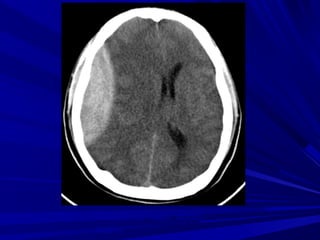

ĐỘT QUỴ THIẾU MÁU

NÃO CỤC BỘ CẤP

GIAI ÑOAÏN CAÁP

GIAI ÑOAÏN CAÁP SÔÙM (6-24 GIÔØ)

-Giaûm ñaäm ñoä ôû haïch neàn

-Maát ranh giôùi chaát traéng – xaùm

-Daáu daûi baêng thuyø ñaûo (insular ribbon

sign)

-Xoaù raõnh naõo

-Khoâng thaáy baát thöôøng